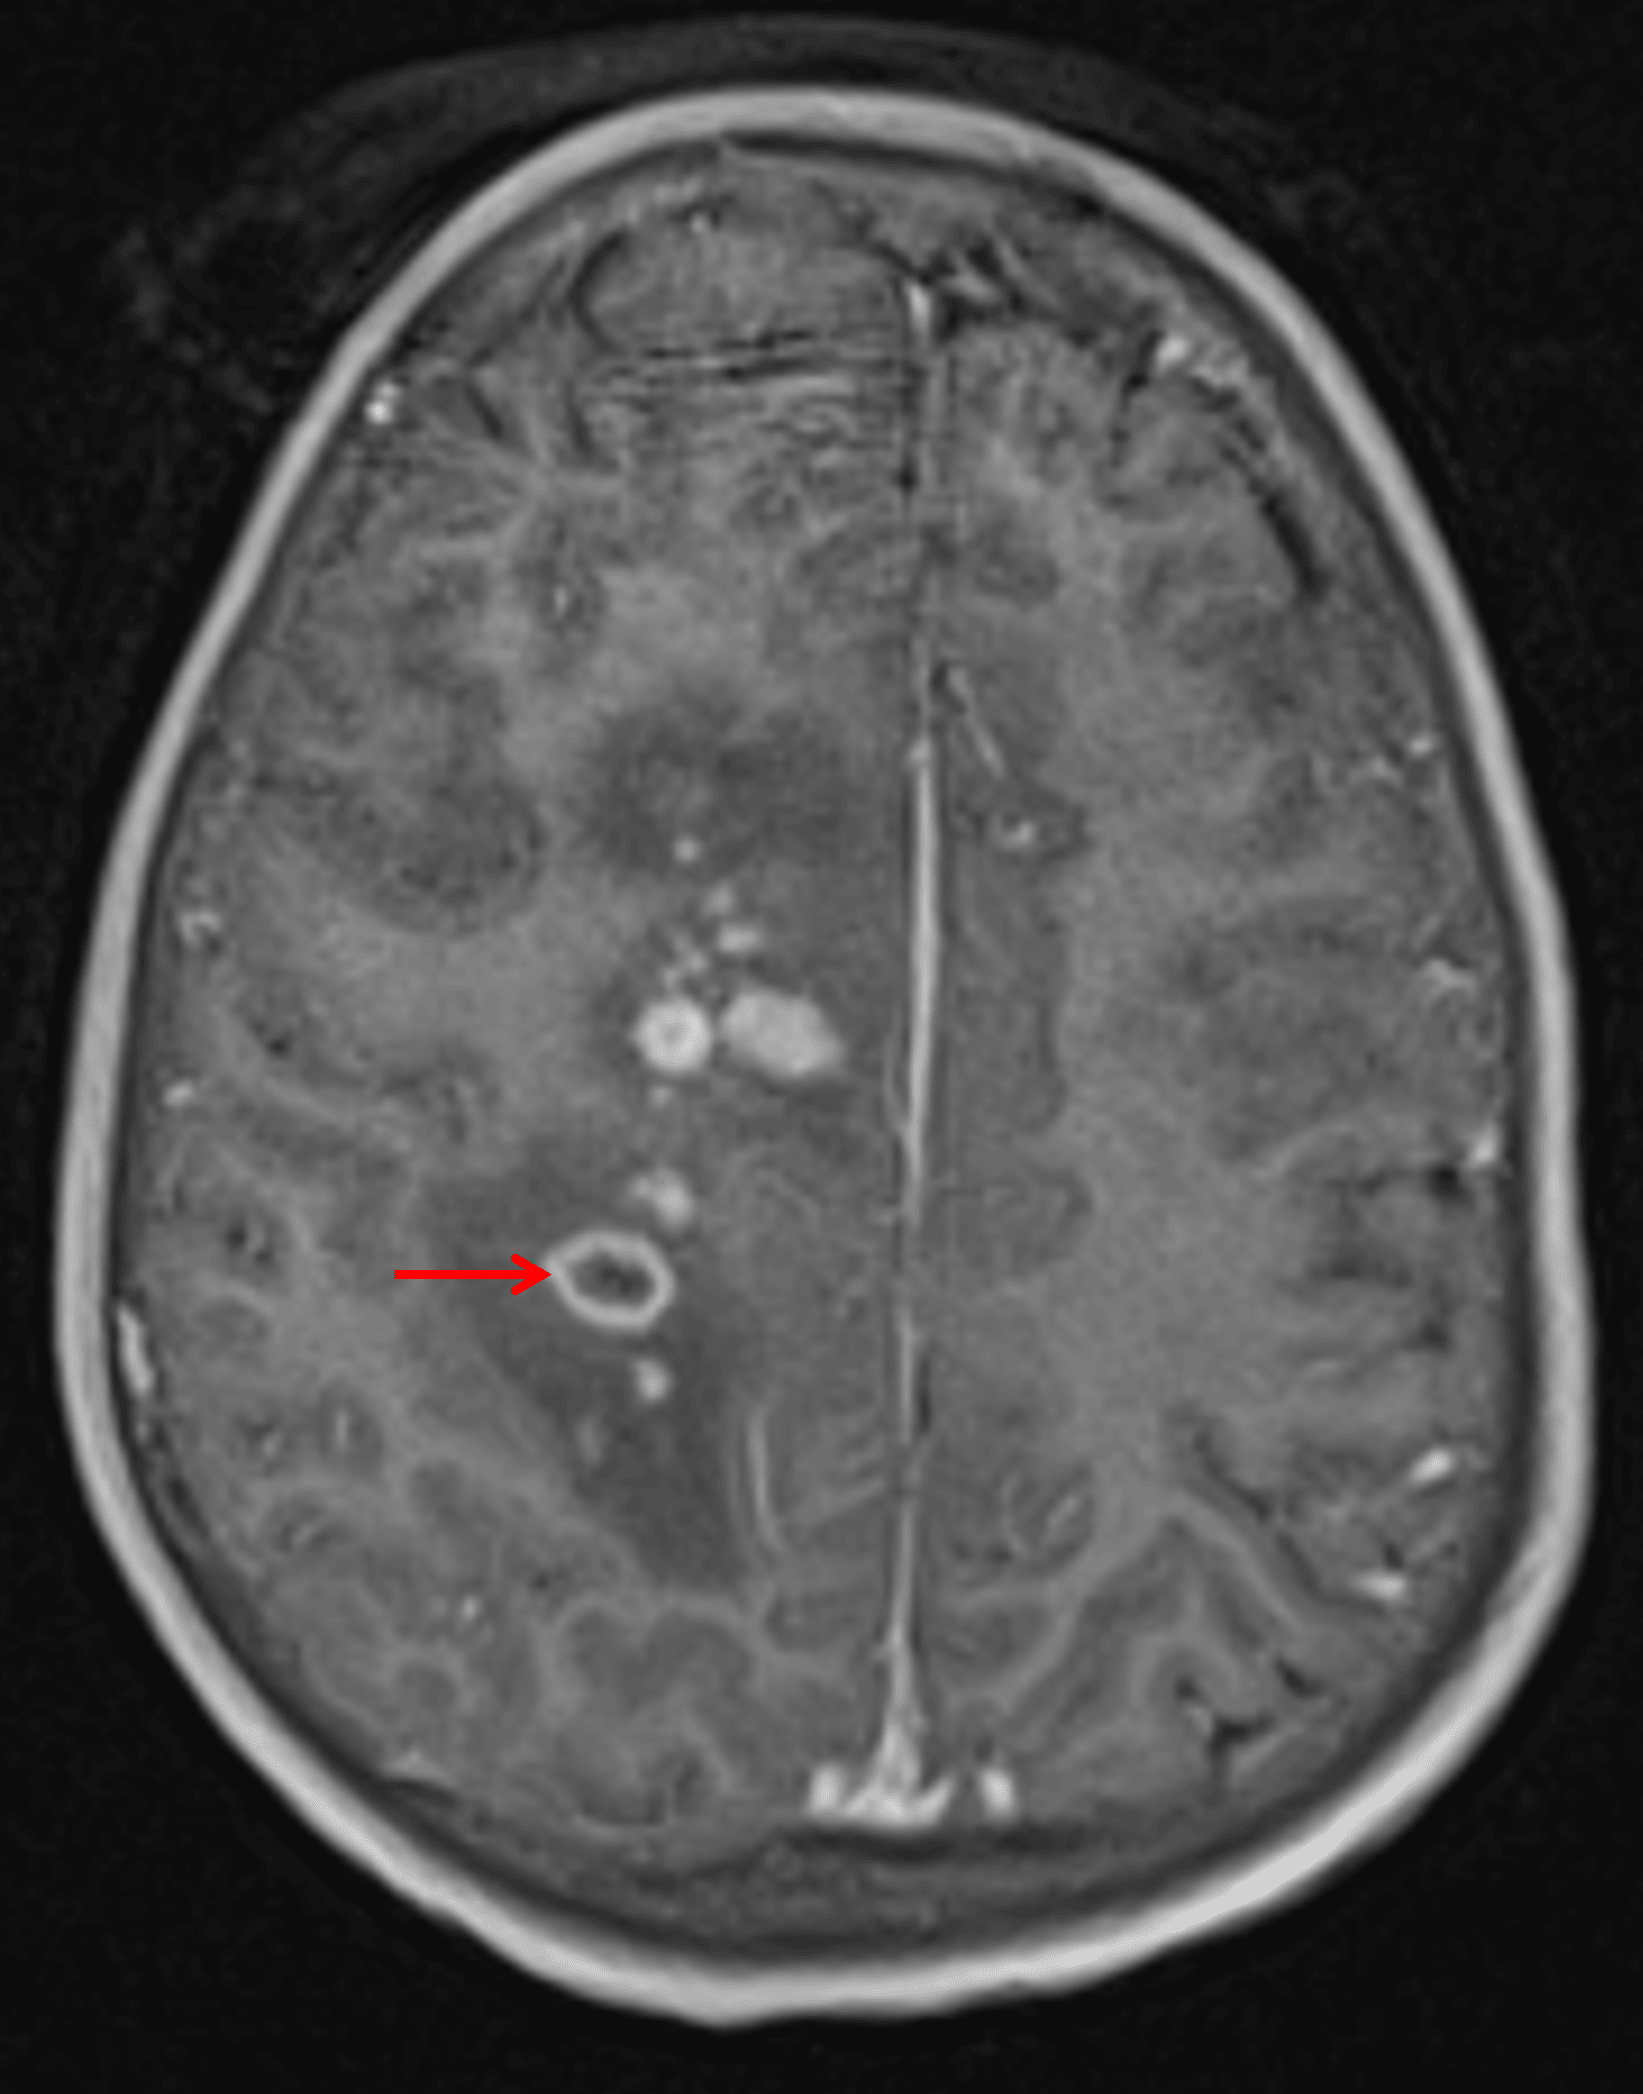

• Numerous enhancing lesions in the bilateral cerebral and cerebellar hemispheres, the cerebellar vermis, and the medulla, many of which are periventricular in location and extend to the ependymal surface of the ventricles

• The majority of these lesions demonstrate solid enhancement, though a few demonstrate peripheral enhancement

Numerous small enhancing lesions are seen. Most solidly enhance, but one in this image demonstrates peripheral enhancement (red arrow).